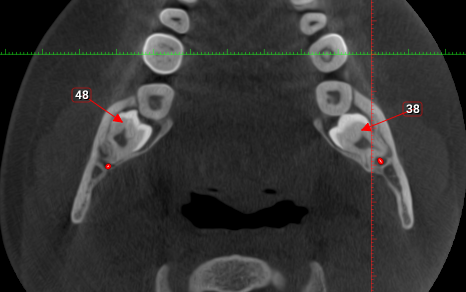

La mayoría de los quistes son hallazgos casuales encontrados tras realizar pruebas radiológicas con un CBCT.

La mayoría de las veces son quistes mucosos (en sol naciente) o quistes simples, también podemos encontrar quistes odontogénicos, embrionarios, quistes óseos o quistes radiculares. El diagnóstico se hace mediante CBCT.